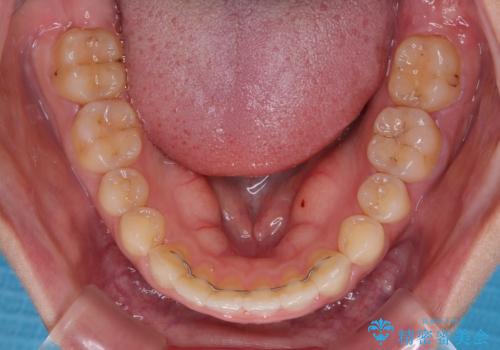

インビザライン矯正で前歯のデコボコを改善

- 前歯のデコボコを気にして来院された患者様です。

目立たないことを最優先にしたいとのことで、デコボコは軽度であったことから、インビザラインにて矯正治療を行うこととしました。

骨格的に下顎骨が左にずれており、上下の正中一致は困難ではありましたが、IPR(歯と歯の間を削る)や後方への移動など組み合わせて、できる限り改善しました。

インビザラインはマウスピースを外している時間が長いと、長期間使用しても前歯のデコボコはあまり改善されません。こちらの患者様は治療期間が長くなり、装着時間が短くなってしまったことで、気になる部分の改善により長期間を要するようになってしまいました。